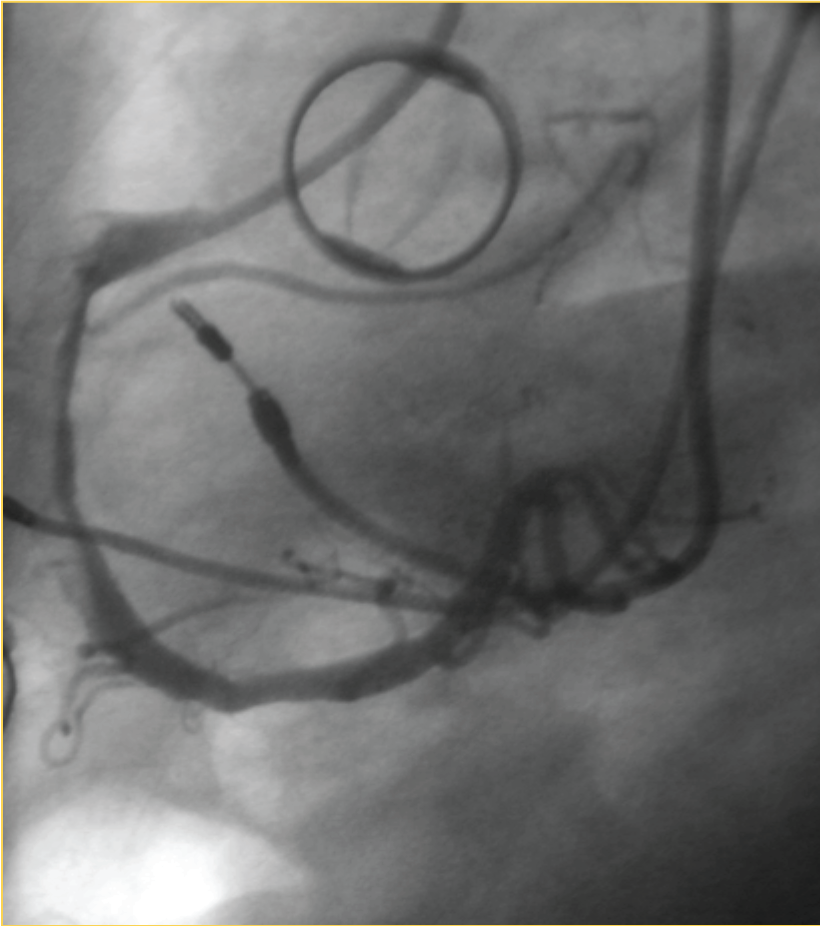

A 74-year-old woman was admitted to our hospital for acute pulmonary oedema. She had undergone aortic valve replacement with a Bicarbon 23A 16years before because aortic stenosis caused by rheumatic valve disease and during the same operation she received a mitral valve repair (commissurotomy) for mitral valve stenosis. Until February 2008 her clinical condition was good. On February 2012 she was admitted in hospital for atrial flutter with high ventricular response. She was treated with amiodarone and than after 4 days she was discharge. Transthoracic echocardiography (TTE) was performed and showed a left ventricle with normal volume and diameter, with ipokinesia of the apex, EF 45%, a normal aortic prosthesis motion, and a native mitral valve with mild stenosis. On March 2012 she was admitted again in our hospital for acute pulmonary oedema, auscultation revealed normal prosthetic valve opening and closing clicks and a grade 2/6 ejection systolic murmur. TTE showed an intermittent aortic prosthesis dysfunction with mean (24mm Hg) and peak (100mm Hg) aortic gradients, they were higher than previous values recorded one month before. Multiplan transesophageal echocardiography (TEE) was, therefore, performed and confirmed TTE data. Severe aortic valve prosthesis regurgitation occurred intermittently and than a pannus or a thrombus was suspected do to a partial occlusion of the leaflets. A cardiac catheterisation (CC) and a cinefluoroscopy (CF) were performed. On CC the coronary artery was without stenosis and the prosthesis valve was good. CF allowed proper visualization of the disks showing normal systolic motion and the prosthesis aortic valve has a good motion of the bileaflet (Figure 1). While the diagnosis of an intermittent aortic prosthesis valve dysfunction was done, the patients were admitted to the operating theatre where she had an aortic and mitral valve replacement. Sternotomy was performed and extracorporeal circulation was started. An aortotomy was done and no pannus or thrombus was seen on the prosthesis but an intimal flap on the aortic wall was found. So the diagnosis of chronic Stanford type A aortic dissection was done. The Aortic dissection involved only the ascending aorta and the proximal part of the aortic arch. We found two tears in this part of the ascending aorta and the descending was free of dissection. In the light of that we suppose that the dysfunction was intermittently why during some cardiac cycle the flap went into the prosthesis and performed the dysfunction with a high gradient stenosis. The aortic valve was replaced with an 23 Carpentier-Edwards prosthesis, and the mitral valve with a n 27 Carpentier-Edwards prosthesis, and the aorta with a vascular prosthesis n 26. The histological exam confirms the macroscopic diagnosis of chronic aortic dissection, a necrosis of the medial layer of the aortic wall was found. After the operation the patient had an uncomplicated recovery and she was discharged on her 7th postoperative day. Ten months later, on follow up, she was in good condition with no valve dysfunction.

Figure 1 Cinefluoroscopic normal opening of the prosthetic valve.